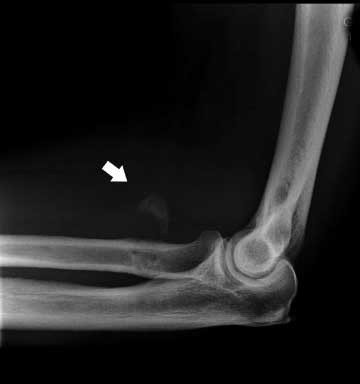

Mynd 3. Beinmyndun í mjúkvefjum hjá 58 ára gömlum manni fimm árum eftir aðgerð.

Sex sjúklingar höfðu merki um beinnýmyndun í mjúkvefjum á röntgenmynd, sjá mynd 3, en enginn þeirra hafði samvöxt á sveif og öln (radioulnar synostosis).